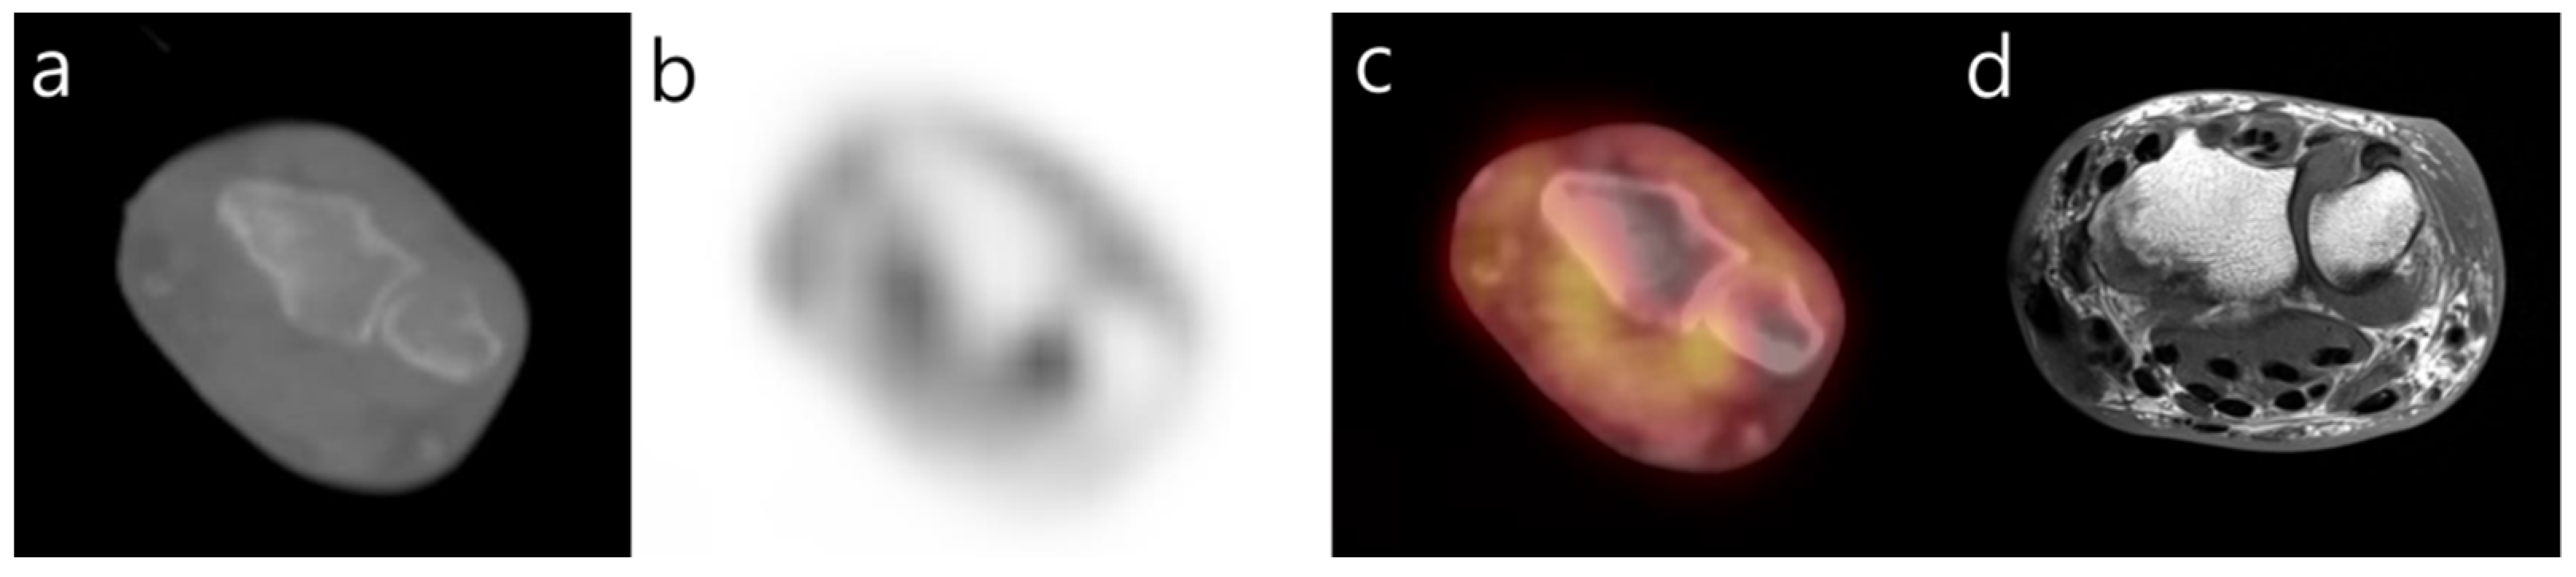

Visualization of Dialysis-Related Amyloid Arthropathy on 18F-FDG PET-CT Scan

Cheon, M.; Yoo, J. Visualization of Dialysis-Related Amyloid Arthropathy on 18F-FDG PET-CT Scan. Diagnostics 2022, 12, 113. https://doi.org/10.3390/diagnostics12010113